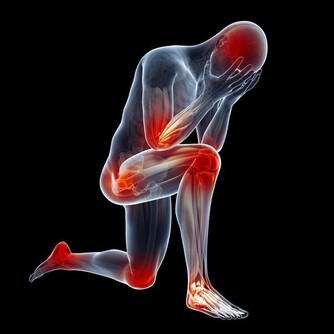

有脂毒的人一般偏胖、脂肪較多,經常喝酒、吃肉、吃油炸食品,對肝臟傷害很大,易得脂肪肝等疾病。想清除脂毒,首先要降血脂,建議用山楂、荷葉煮水喝,可化痰降脂;平時應多吃洋蔥等蔬菜;還可按揉小腿上的豐隆穴(位於外踝尖上8寸,條口穴外,距脛骨前緣二橫指處),可以消食導滯,減少脂肪。 5、瘀毒 瘀毒是指藏在血液里的毒,大多是從中年開始出現的,一般表現為舌下脈絡發紫、容易健忘、皮膚乾燥、胸悶憋氣、臉色暗等。有瘀毒的人,也可以用丹參或山楂泡水喝,可以活血化瘀,清除血管垃圾。 6、氣毒 氣毒是存在肺裡面的毒,中醫認為「肺主氣」、「腎主納氣」,有氣毒的人往往肺腎功能不好,一般身上氣味大,如有口臭、汗臭等。為了防止氣毒,可以每天早起做深呼吸,即「呼吸吐納」,把肺中的濁氣排出來,保持體內空氣的新鮮。

值得提出的是,肝是人體最大的排毒工廠,想要祛除毒素,要從根本上保肝養肝,使之能解毒排毒。建議經常用枸杞、菊花泡水喝,多吃桑葚,以及各類新鮮蔬菜。 日常生活中如何排毒 可別小瞧了這六種陰毒,如果這些毒素在我們的體內越積越多,那麼就會引起各種身體疾病,加速人的衰老。肝臟、腎臟和肺部是身體中最大的解毒器官,要想徹底排出身體的毒素,必須要保養好這些器官。除了上述排毒方法,在日常生活中應該如何排毒呢? 1、定時排便 便秘的滋味確實不好受,長期便秘也會讓我們的腸道積累大量的毒素,引起各種身體疾病。生活中我們除了要注意健康均衡的飲食外,還要養成定時排便的好習慣。無論身體有沒有便意,早上起床後都可以到馬桶上坐一會兒,培養自己的便意。時間長了,這樣就可以養成晨起排便的習慣。 想要定時排便,還可以按摩身體上的「排便穴」。這個穴位位於食指關節的尺側凹陷處,只要按摩一兩分鐘,身體就會產生強烈的便意。 2、堅持運動 現在很多人每天都忙於工作和應酬,很難抽出時間來運動健身。其實,要是能堅持每天都鍛鍊身體,這樣也可以幫助我們輕鬆排除體內的毒素。 比如:跑步、游泳和瑜伽等等。經常運動可以增強人的心肺功能,還能夠促進體內的血液循環。如果在運動過程中適量地補充一些水分,還可以加速身體排出毒素。 3、多吃素 我們每天都要攝入大量的食物,食物進入腸道後,一般要停留兩三天的時間。如果攝取過多的高糖、高脂肪和高膽固醇的食物,那麼身體就不容易消化,產生宿便。宿便對身體的危害非常大,可以使毒素在腸道中被二次吸收。 要想身體不積累毒素,可以多吃點素,少吃點葷腥。可以在一個星期當中選擇一天專門吃素食,這樣可以幫助我們清理腸胃。平時可以多吃點新鮮的瓜果蔬菜,因為這些食物中富含纖維素,可以促進人的腸胃蠕動,幫助身體把宿便排出去。 4、保持好心情 現在人們的生活節奏越來越快,工作壓力也比較大。如果長期處於精神緊張的狀態,就會影響五臟六腑的正常運行。很多時候我們生病都是因為工作壓力大和精神緊張導致的,因此,大家要放慢生活節奏,保持愉悅輕鬆的心情。 5、不熬夜 都說熬夜就是慢性自殺,熬夜對人體健康的傷害特別大。在晚上,身體的大部分器官都會進行排毒工作。如果晚上不睡覺,那麼排毒器官就會罷工。長期熬夜就會導致分泌系統紊亂,新陳代謝功能出現障礙,身體也會產生各種各樣的毒素。要想徹底排除體內的這些毒素,就要養成良好的作息習慣,保證充足的睡眠,儘量不要熬夜。 健康養生的第一步,讓我們排出毒素開始吧! -